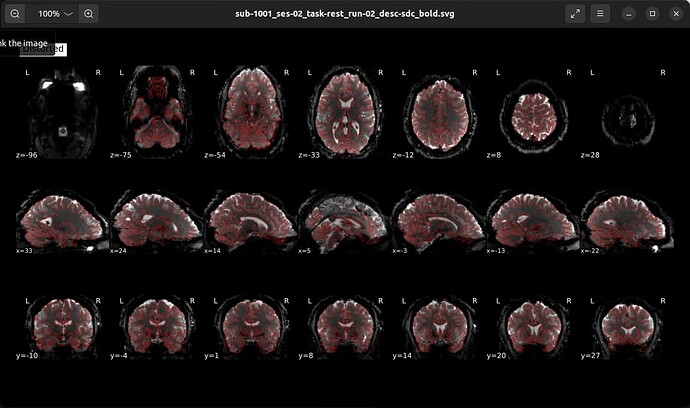

The data has been converted to BIDS and preprocessed using fMRIprep.

As I was checking the ROI overlays for my subjects’ BOLD data (which has been registered to MNI152NLin2009cAsym space) I noticed that the signal in the orbitofrontal cortex (OFC) on the PA-acquired image is much worse that that on the AP acquired images. Here is an example of what I mean:

This is concerning to me, because I am interested in the medial OFC (mOFC) as one of my ROIs. I am also interested in areas of the hindbrain as part of my analyses.